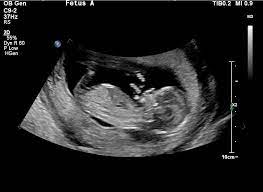

13. Haftada bebeğinizin ortalama boyu 9 cm. ve ağırlığının da 26 gram olması beklenilmektedir.

Bu dönemde tepe denilen oluşumun ultrasondaki görünümüne göre erkek bebeklerde yukarı bakan, kız bebeklerde ise vücuda paralel olarak bir gelişim izlediği görülür. Bu dönemde bebek ancak bir şeftali büyüklüğü kadar gözlemlenir ve fark edebileceğiniz en büyük ayrıntı bacaklarının kollarından daha uzun olduğudur. Organ gelişimi tamamlanmış olan bebeğin bundan sonra geçireceği değişiklikler büyümek olacaktır.